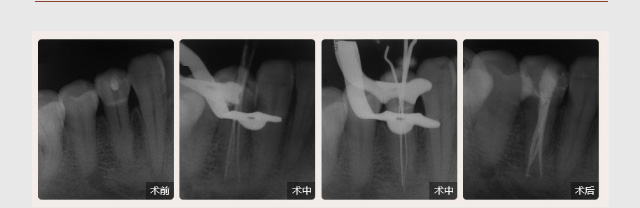

性别: 女年龄: 26岁

牙齿症状:急性牙髓炎(左下烂牙近一周自发性、阵发性疼痛)

治疗方法:显微根管治疗

疑难点评:填充严密、各根管均恰填,高质量地完成了弯曲根管和S形根管的治疗,体现操作者优秀的临场操作能力。

性别: 男年龄: 55岁

牙齿症状:急性牙髓炎(左下牙自发性、阵发性痛3天)

治疗方法:显微根管治疗

疑难点评:操作方面使用根管显微镜和超声波系统细致寻找和定位根管,根管的敞开度较为完美,维持了根管的原有走向,充填致密,流畅,充填长度准确。